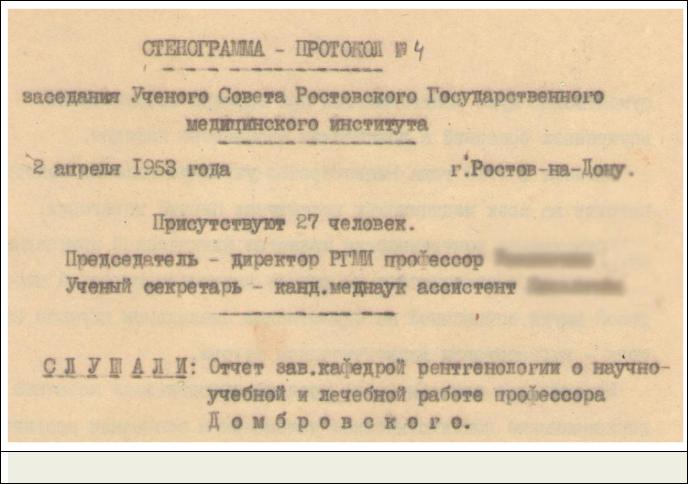

документов и, в первую очередь, из стенограм- |

мы заседания Ученого совета, прошедшего 2 |

апреля 1953 года в РГМИ (Рис. 2). Она также |

Вот на таком фоне и проходил 2 апреля 1953 года тот Учѐный совет Ростовского медицинского института, стенограмма которого совершенно случайно попала мне в руки.

Рис. 2. Фрагмент стенограммы заседания Ученого совета РГМИ, апрель 1953 г.

Рис. 2. Фрагмент стенограммы заседания Ученого совета РГМИ, апрель 1953 г.